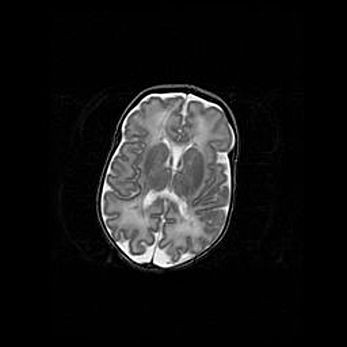

Церебральная ишемия II.

Возраст: 5 дней

Вес: 3400 г

Пол: женский

Окружность головы: 35 см

Срок гестации: 39 недель

Церебральная ишемия – это заболевание, характеризующееся недостаточностью (гипоксией) либо полным прекращением (аноксией) снабжения мозга кислородом по причине закупорки одного или нескольких сосудов. Это приводит к  что метаболическим расстройствам различной степени тяжести в тканях головного мозга, развитию коагуляционных некрозов и гибели нейронов.